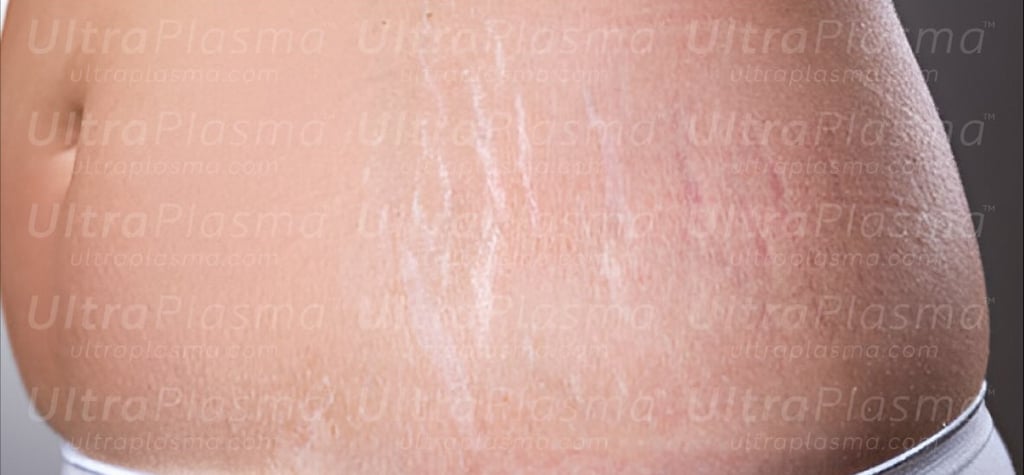

Scarring, a complex biological response to dermal injury, manifests in various forms including surgical, hypertrophic, keloid, atrophic, stretch marks (striae), and umbilical scars. Traditional treatments often fall short due to the variability in scar biology and patient response. UltraPlasma™, a next-generation dermatological technology integrating arc, argon, and helium plasma modalities, offers a multi-depth, multi-function strategy. This article explores the anatomical, biological, and engineering principles behind scar remediation using UltraPlasma™, including the effects on skin layers, reactive species interactions, and clinical applications.

Scars can result from trauma, surgery, acne, burns, or infections. Classified as:

5.4 Striae Distensae

Helium plasma to stimulate dermal thickening and elastin formation.

Gradual melanocyte repigmentation with ozone modulation.